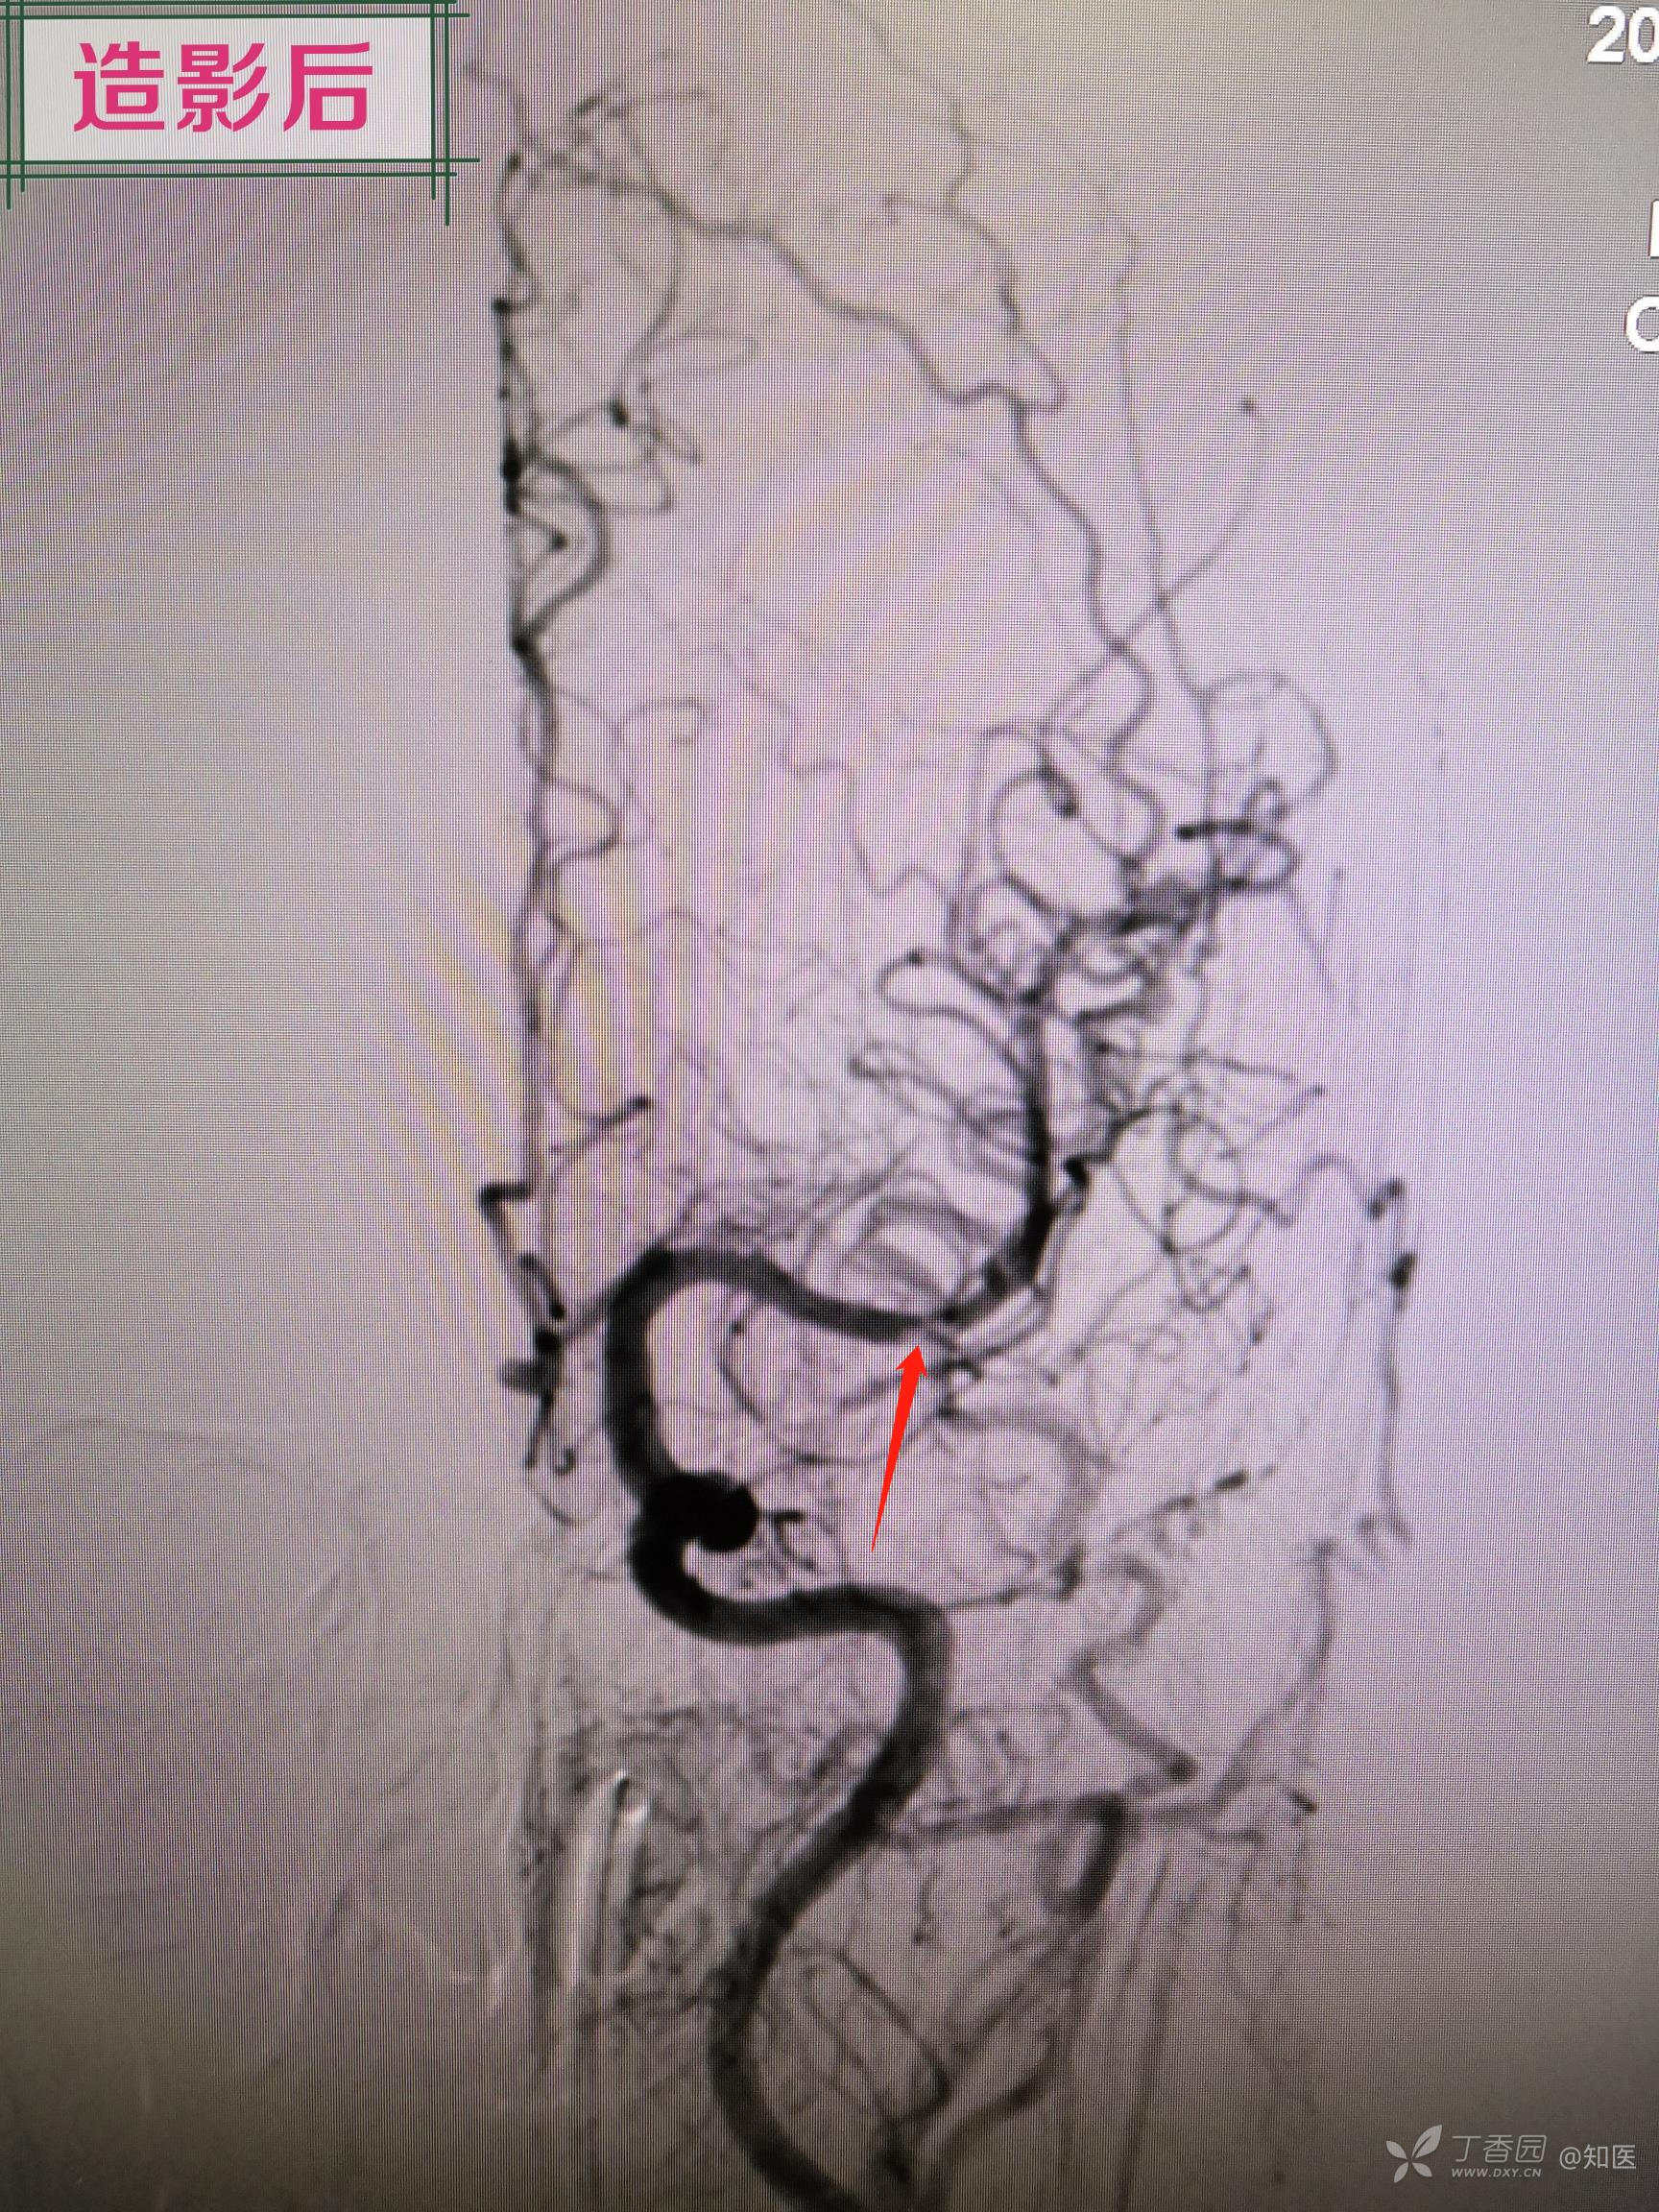

简述手术过程:采用同轴技术将8FGuiding置于左侧颈内动脉颈段,造影显示左侧大脑中动脉M2段局部白色血栓样病变,微导丝及微导管导引下将6F中间导管置于左侧大脑中接近白色血栓样病变,经中间导管尾端负压抽吸未见回血,持续负压吸引下将中间导管回撤至颈内动脉末端后,回抽未见血栓,再次造影显示左侧大脑中动脉完全闭塞,主手术者考虑血管内膜受损所致夹层闭塞。更换微导丝配合微导管通过闭塞段,将微导管置于闭塞远端,撤出微导丝,经微导管造影确认真腔,交换长导丝将1.5mm-15mm球囊置于狭窄段(局部白色血栓样病变段),给予8ATM扩张,造影见局部白色血栓样病变段90%狭窄,远端血流恢复,经导管给予欣维宁10ml,观察15min,再次造影见残余狭窄仍有90%,贴覆3.0mm-15mm支架于狭窄段,再次造影见残余狭窄约80%,支架覆盖部位造影显示仍有白色类似血栓样病变。由于多次使用及更换微导丝探测,微导丝进入左侧大脑中远端分支,远端分支血管周围可见造影剂外渗,未来得及中和肝素,患者呕吐咖啡色样胃内容物,血氧饱和度下降,心率增快,生命体征不平稳,向家属告知手术结果后终止手术。

询问另一位临床经验丰富神经介入二线医师:左侧大脑中动脉M2段局部白色血栓样病变考虑血栓。但是询问负责该患者主管手术二线考虑夹层样次全闭塞。